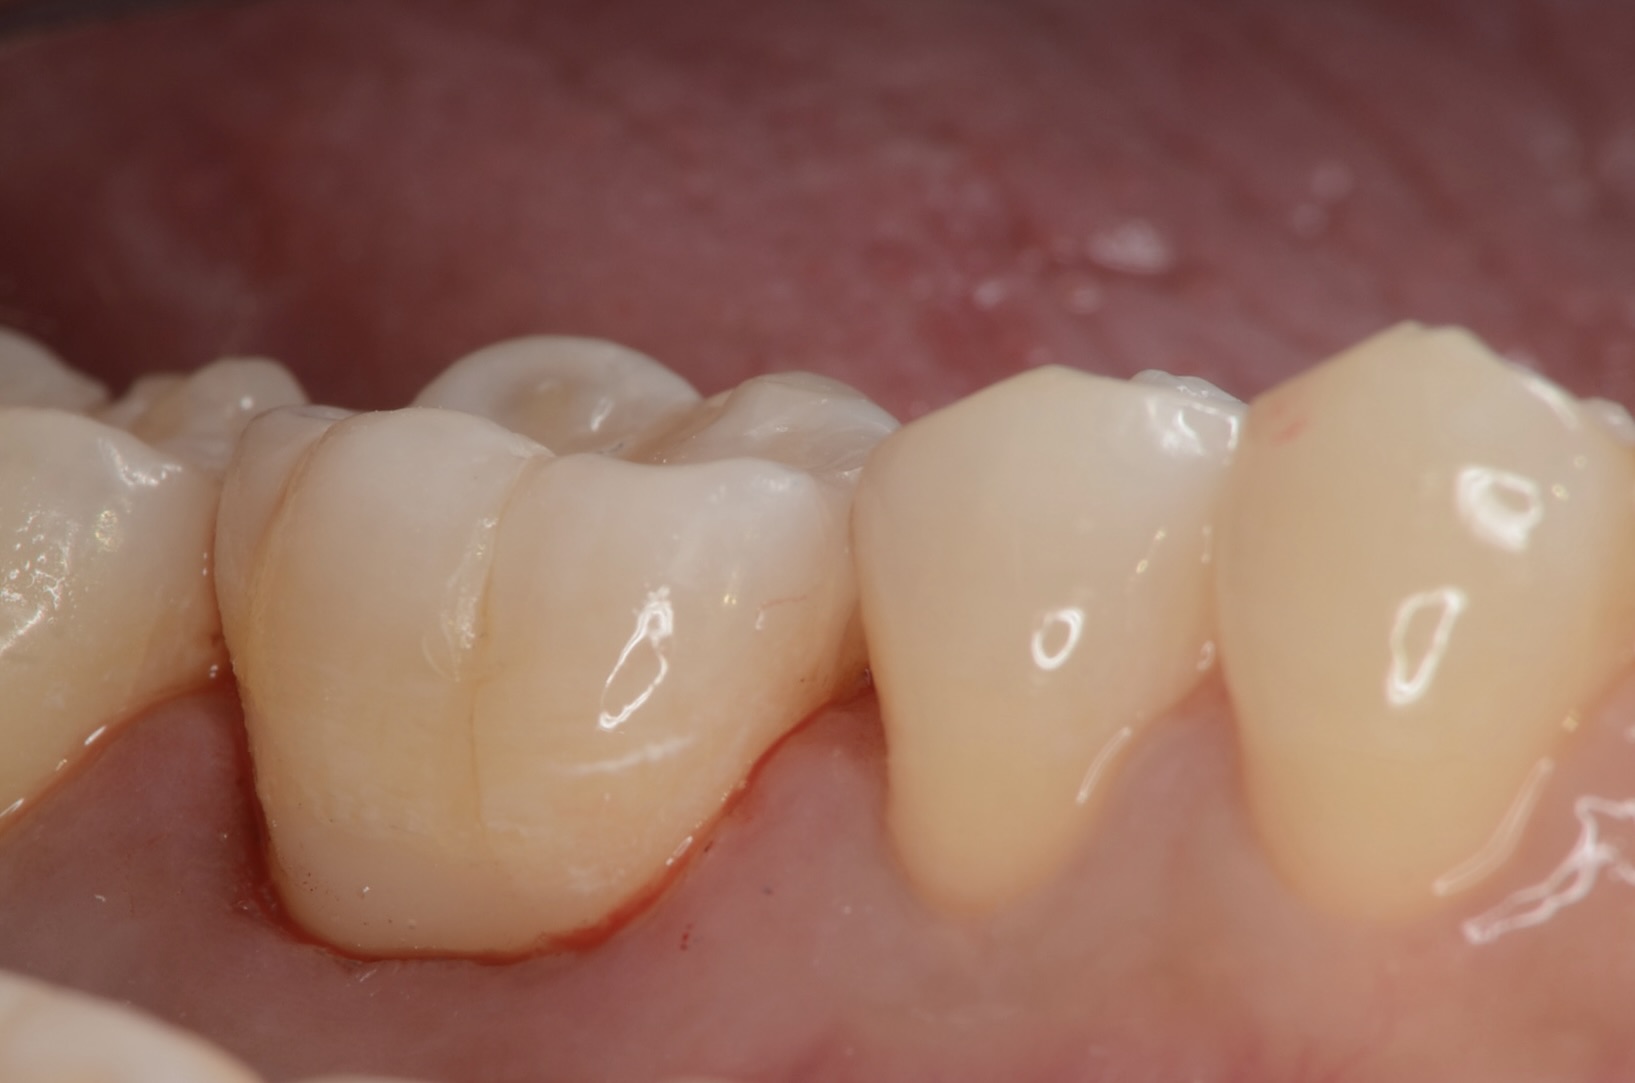

頬側面観

滑らかに仕上がっています。 -

歯頸部のレジン除去

歯肉縁下に虫歯があったので、ラバーダムを外してZooという唾液を吸い取るチューブを使って乾燥させながら治療しました。 -

歯頸部のレジン充填

ツルツルに研磨します